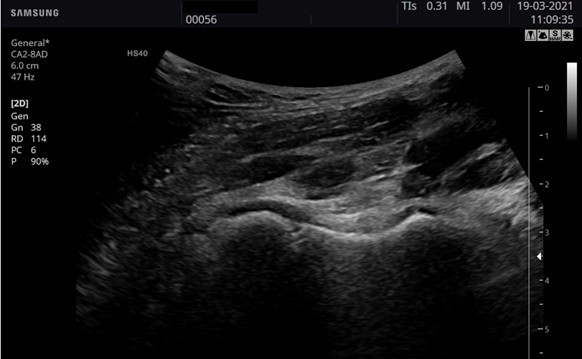

Imagen

Imatge ecogràfica en Mode B (2D)